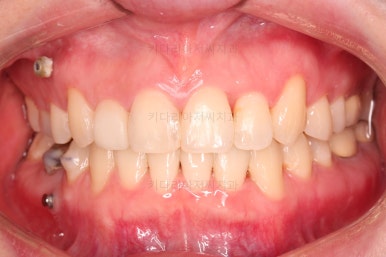

적절하게 디테일을 손보고 마무리를 합니다.

중간중간 보철된 치아도 있고, 위아래의 중앙선까지 100% 맞기는 힘든 상황이었지만 가급적이면 매우 잘 맞춰 드렸고요.

교합이라던지 가지런한 느낌도 좋네요.

우측만 위아래 뽑았지만 기능에는 문제 없이 교합을 마무리 했습니다.

부산치과교정 전후사진을 비교해 볼게요.

발치교정이라고 입매가 들어간 것도 아니고 오히려 더 예뻐졌죠?

중심선도 원하시는만큼 갖추었고, 가지런한 느낌도 좋고요.

21개월만에 전반적으로 매우 만족할만한 치료 결과를 얻었습니다.